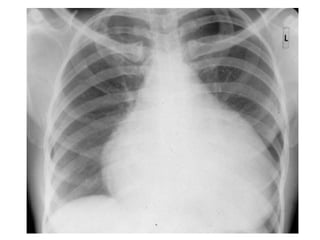

• Pericardial effusion------------

tampnade